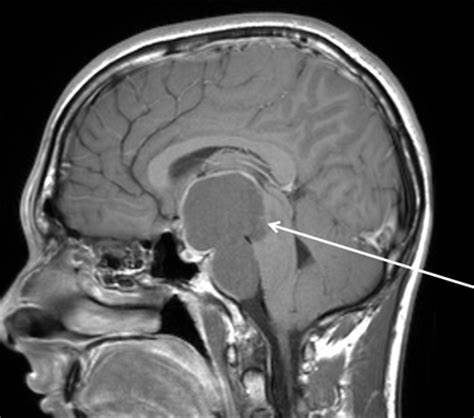

儿童期出现的颅咽管瘤通常延伸至鞍上区,在大多数情况下,需通过显微外科经颅入路切除。对于地形和解剖原因,蝶手术具有不会干扰下丘脑功能的优点。除了经典的前外侧入路外,神经内镜手术在颅咽管瘤的神经外科治疗中也越来越受欢迎。

对于局部定位良好的肿瘤,优选的治疗方法是尝试完全切除并保留视力,下丘脑和垂体功能。对于局限性肿瘤,是否仍应尝试完全切除还是计划进行有限切除(活检,部分切除或小计切除)存在争议。由于手术引起的缺陷(主要是下丘脑)的风险以及尽管显然已完全切除的婴幼儿复发率很高,许多专家对这些情况下的计划性根治性手术持批判性看法。